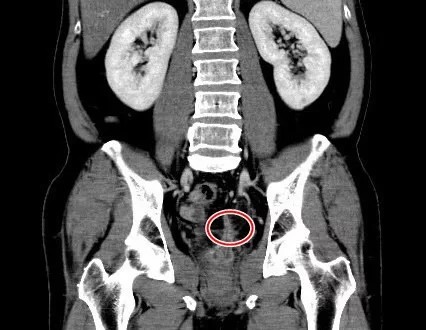

收治病例的高雄長庚醫院大腸直腸科主治醫師鄭功全表示,發著高燒的男子由他院轉到該院急診室時,已併發敗血症,在其腹部電腦斷層影像中,可看到男子直腸附近有膿瘍,另有個細微柱狀的陰影,懷疑是異物穿刺,隨即推他進手術室開刀。

鄭功全為男子開刀時發現他的直腸處有段潰瘍,予以清創發炎組織和膿瘍後,發現一根枝狀物穿出直腸,將其取出來,發現是一根長3.5公分的魚刺。